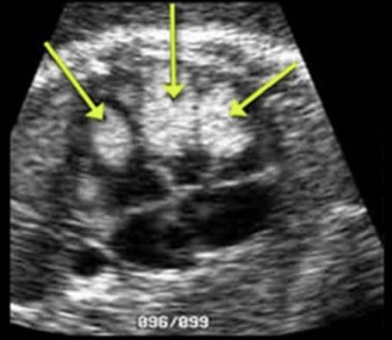

this is frog eyes aka anencephaly

d) AFP